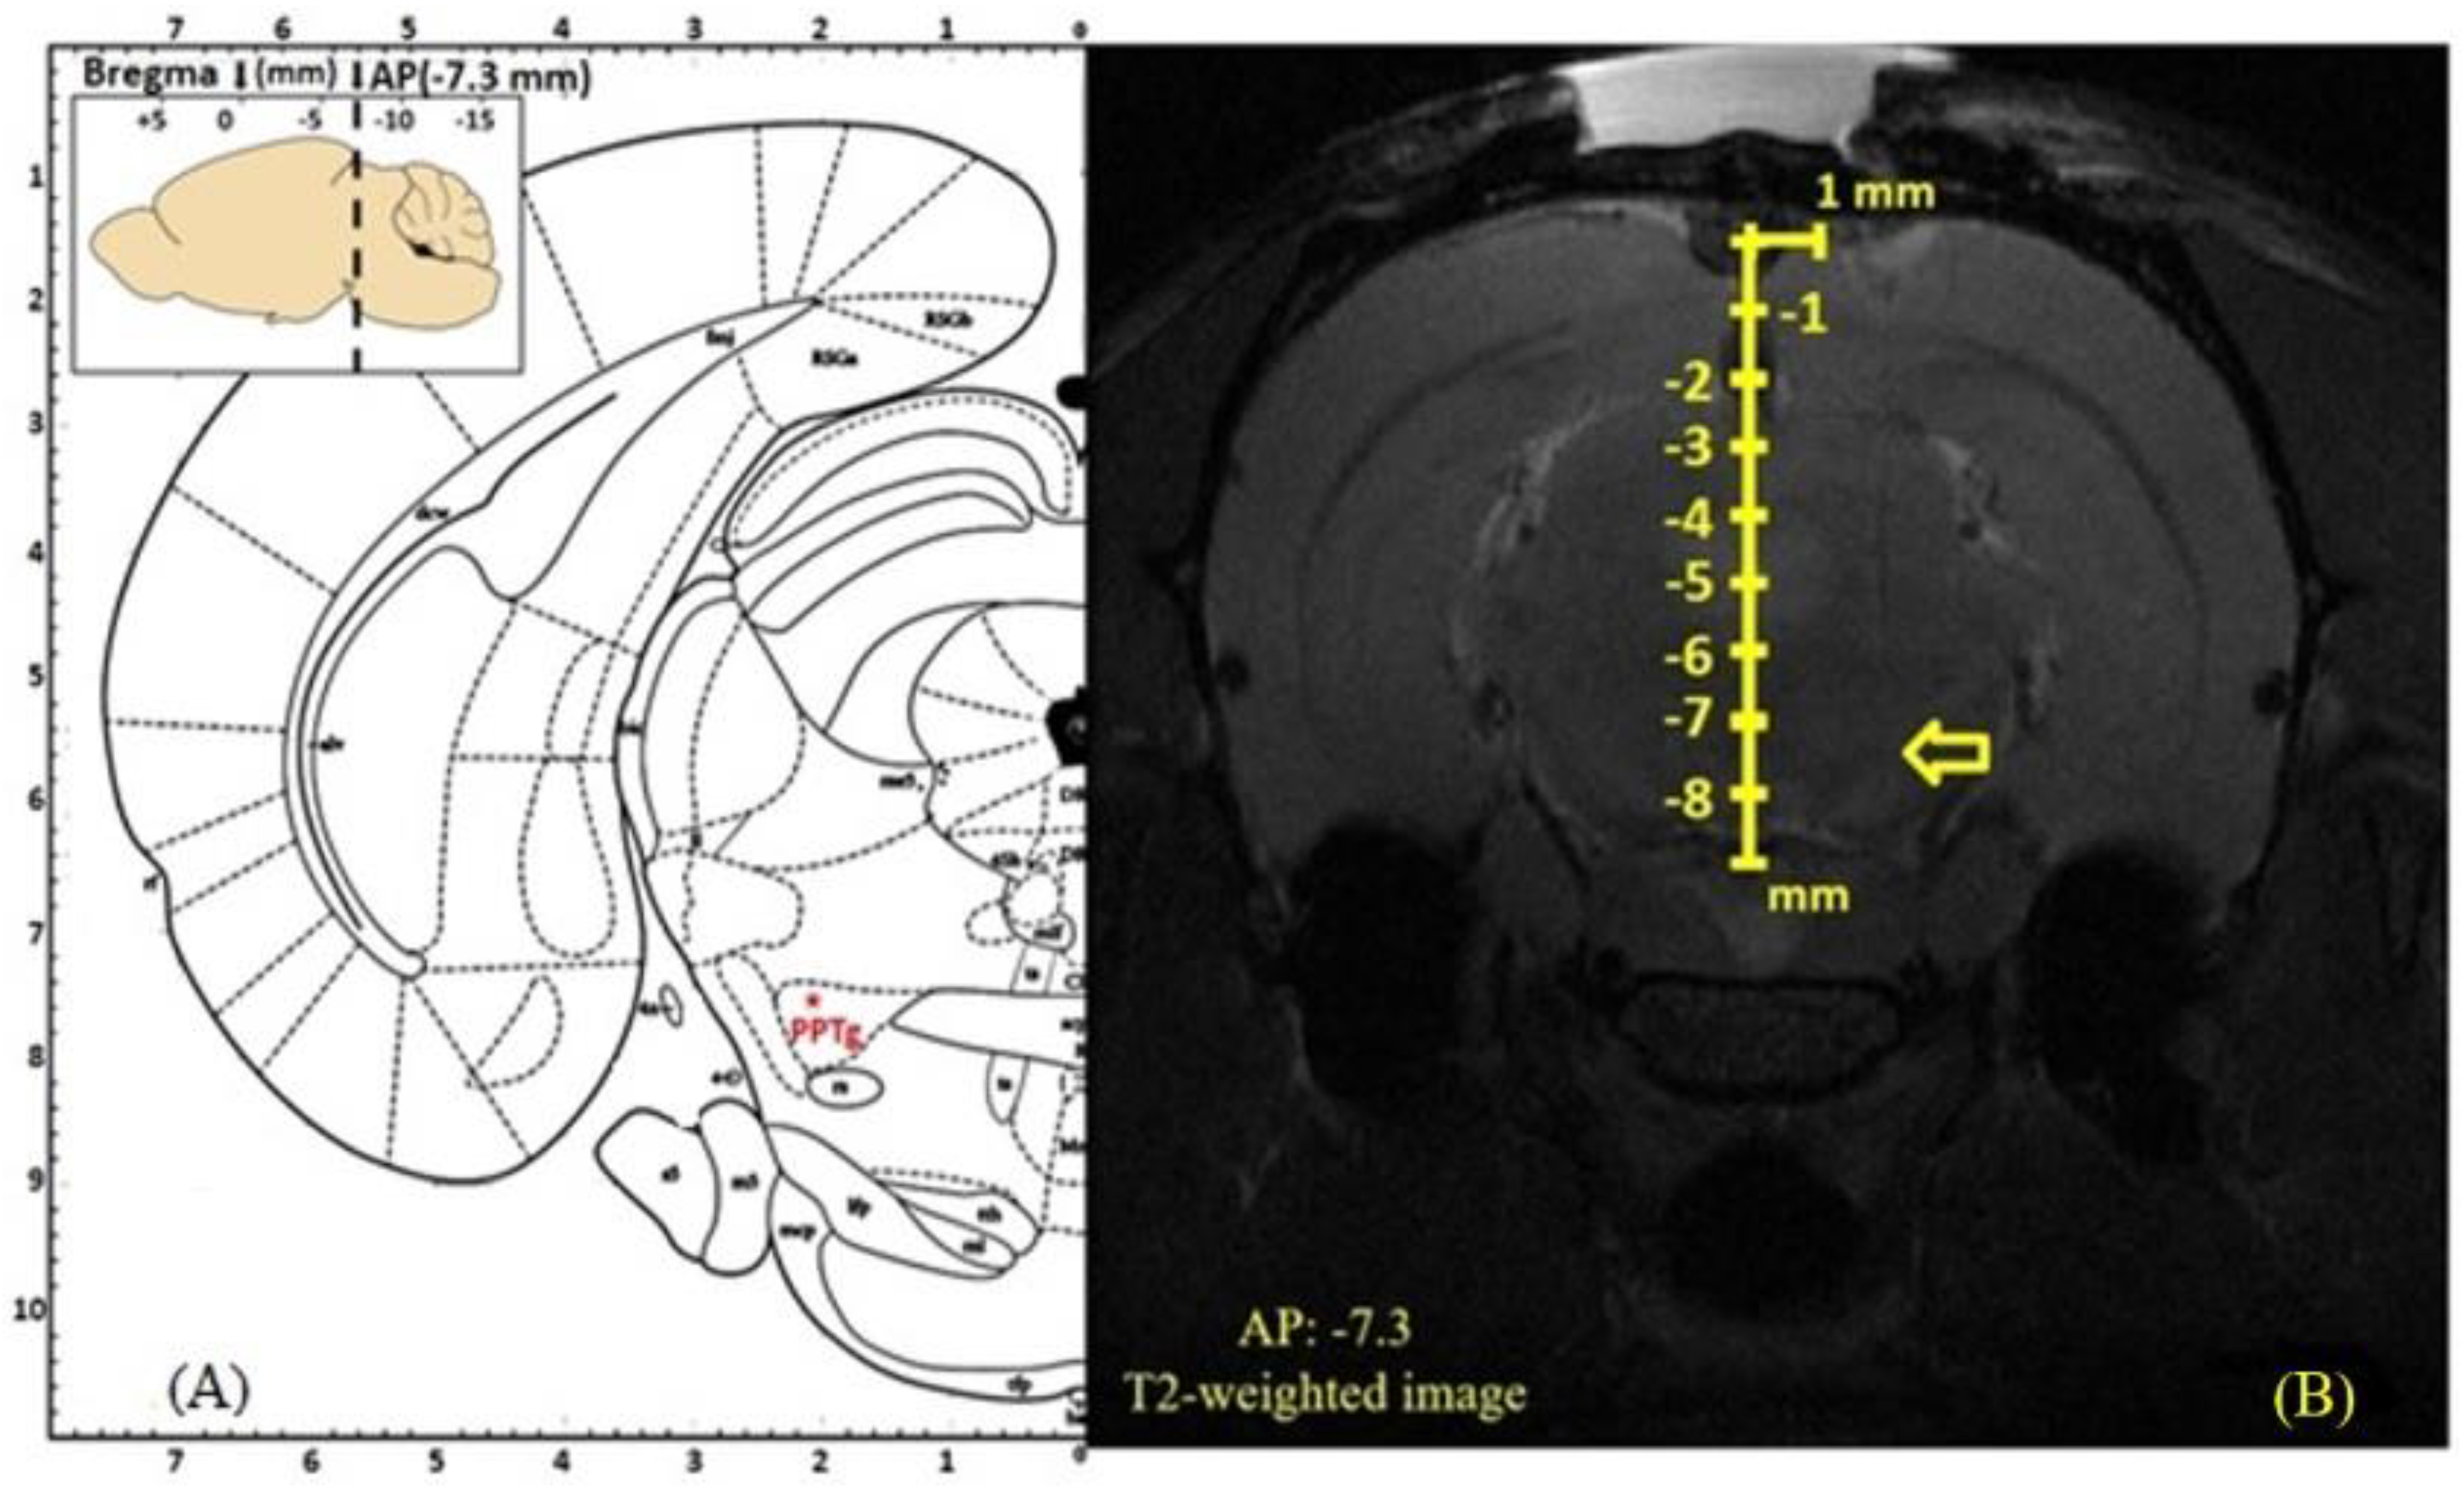

2.1.4. Stereotactic Procedures and Deep Brain Stimulation Protocols

2.1.5. Magnetic Resonance Imaging to Assess the Deep Brain Stimulation Electrode Location

- Paxinos, G.; Watson, C. The Rat Brain in Stereotaxic Coordinates; Academic Press Elsevier: Amsterdam, The Netherlands, 2006. [Google Scholar]